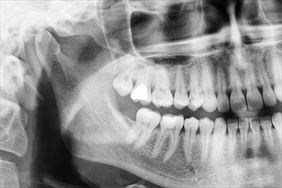

Rentgenodiagnostyka stomatologiczna odgrywa kluczową rolę w precyzyjnej ocenie stanu zdrowia zębów, kości szczęki, żuchwy oraz zatok szczękowych. Dzięki obrazowaniu radiologicznemu możemy wykryć zmiany niewidoczne gołym okiem, takie jak próchnica pod wypełnieniami, ubytki strukturalne, stany zapalne czy torbiele. Zdjęcia rentgenowskie są również niezbędne przy planowaniu leczenia ortodontycznego, implantologicznego oraz chirurgicznego.

W naszym gabinecie wykonujemy różne rodzaje zdjęć RTG, w tym:

• zdjęcia panoramiczne,

• zdjęcia punktowe,

• zdjęcia cefalometryczne.